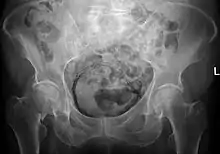

| Regulation of urine production by ADH and aldosterone | |